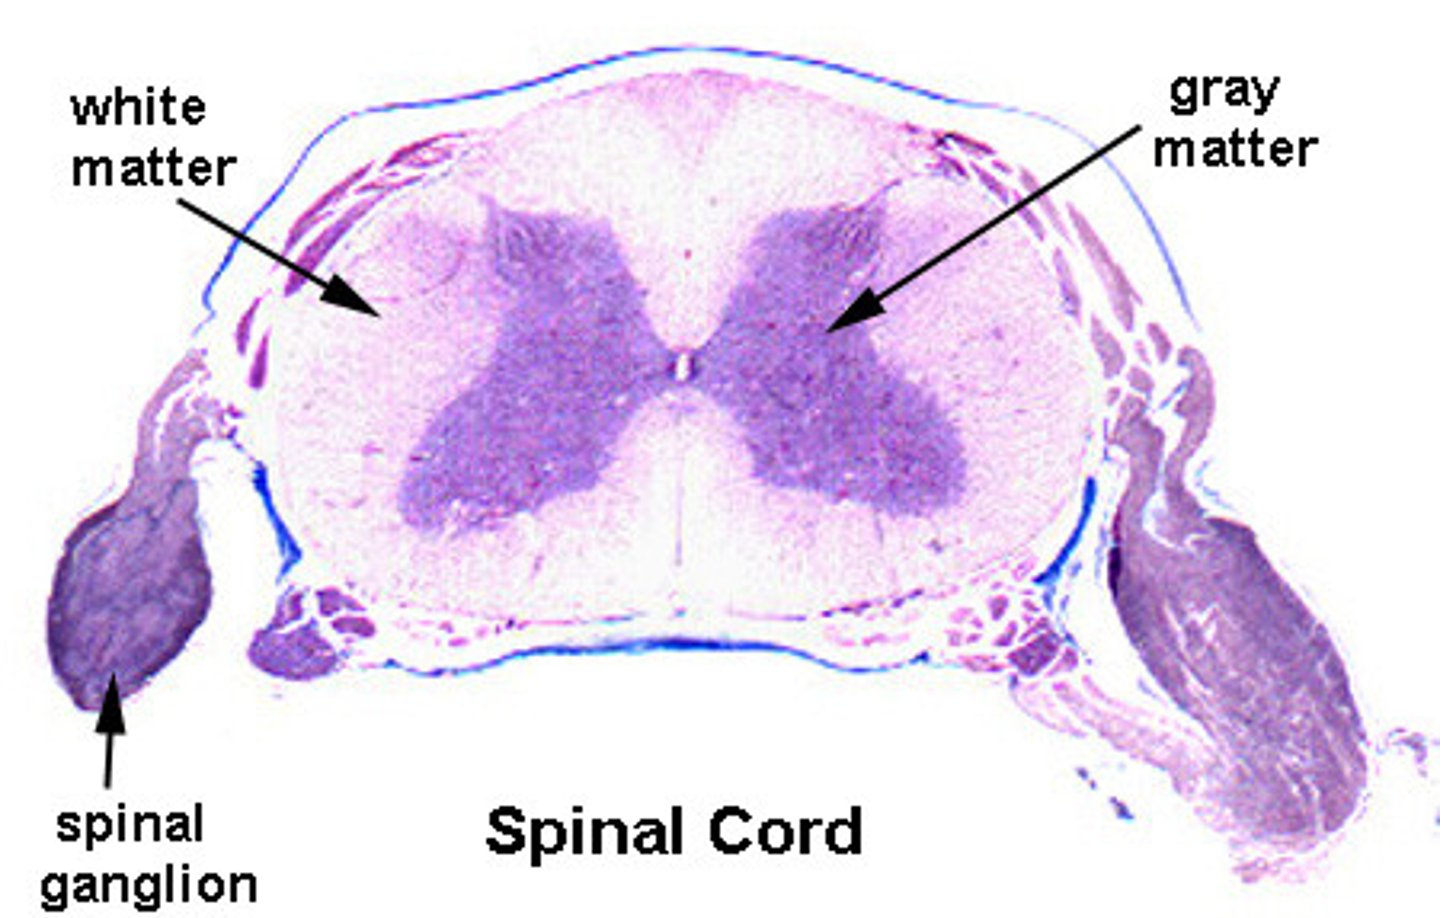

white matter of spinal cord

Primarily myelinated axons, but also has unmyelinated axons

Contains major sensory and motor tracts to and from the brain

gray matter of spinal cord

Mostly neuron cell bodies, neuroglia, unmyelinated axons

Has central canal in the middle - contains cerebrospinal fluid

Posterior Root

Carries sensory neurons

posterior root ganglion

Contains sensory nerve cell bodies

Anterior root

carries motor information